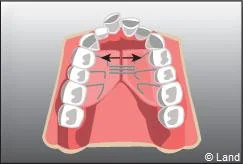

De plus, il est opportun de corriger très tôt certaines malpositions. Les appareils généralement utilisés sont amovibles avec une armature en résine, mais peuvent aussi être fixes à l’aide de bagues sur les premières molaires définitives.. Suivant leurs conceptions et la manière dont ils sont portés, ils auront une action sur la position des dents mais aussi sur la croissance.